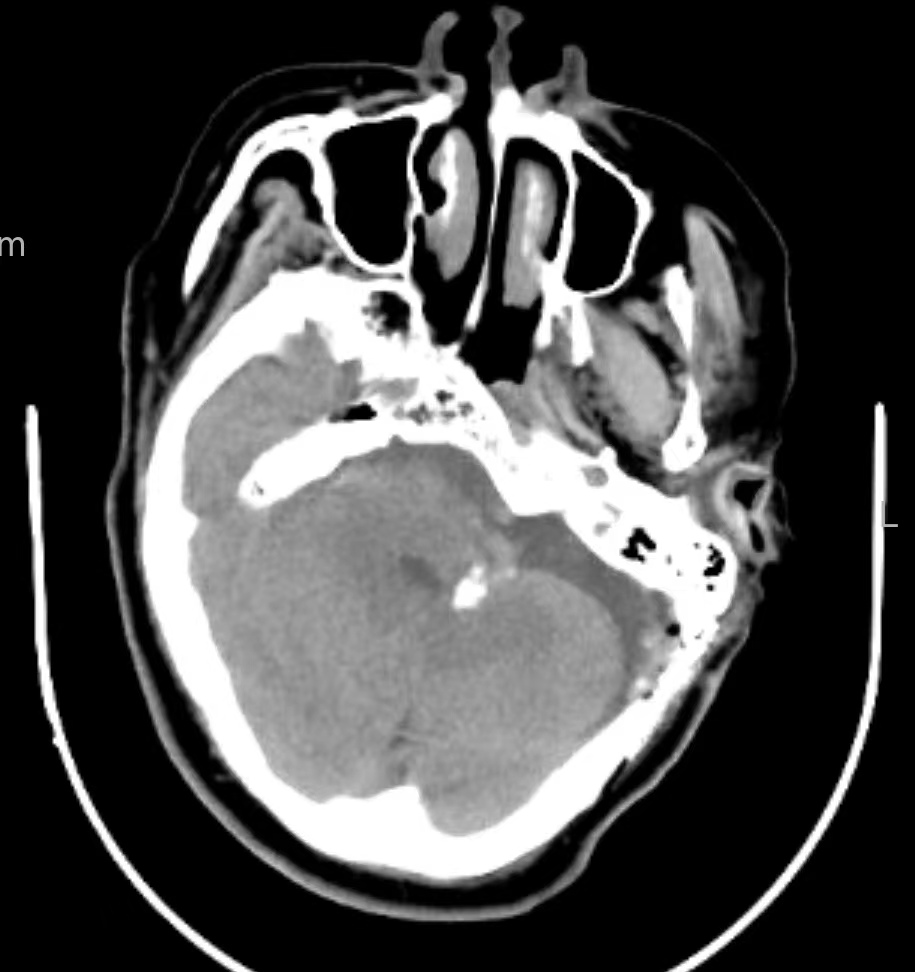

该例特点:术中见既往垫片与后组颅神经、血管粘连,硬化机化严重,剪刀、剥离子均无法撼动丝毫。

逐渐解剖,最终从后组颅神经尾端分离到操作空间,见到腹侧下方REZ区有血管卡压后组颅神经REZ区。充分松解后垫入teflon垫片,术后疼痛完全消失。

微血管减压术后复发原因可能有:早期复发与垫片漂移、垫片不到位;晚期复发可能与垫片机化粘连、其他血管卡压、蛛网膜粘连等因素有关。